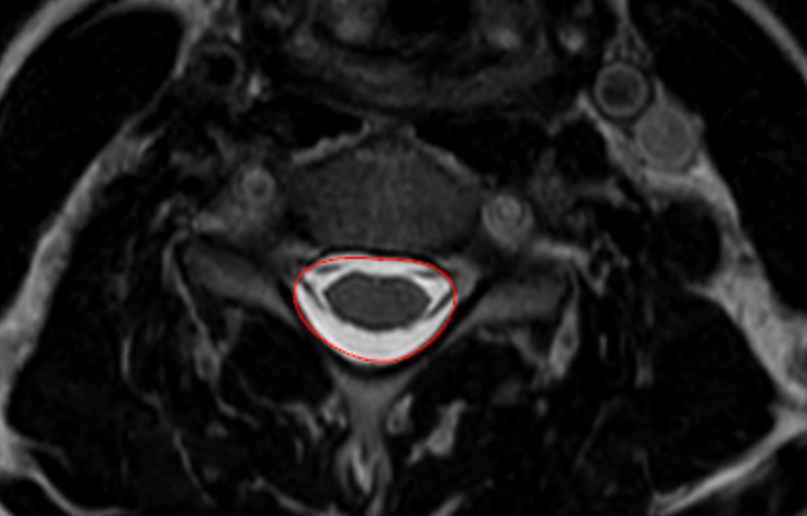

Image Type Cervical Spine X-Ray CT Scan MRI Scan Compression Ratio (AP diameter transverse diameter of cord) Cord Cross-Sectional Area (CSA) Cross-Sectional Canal Area Maximum Spinal Cord Compression Pavlov/Torg (Canal-Body Ratio) Sagittal Canal Diameter Spinal Cord Signal Change - T1 Hypointensity Spinal Cord Signal Change - T2 Hyperintensity (+ number of levels)